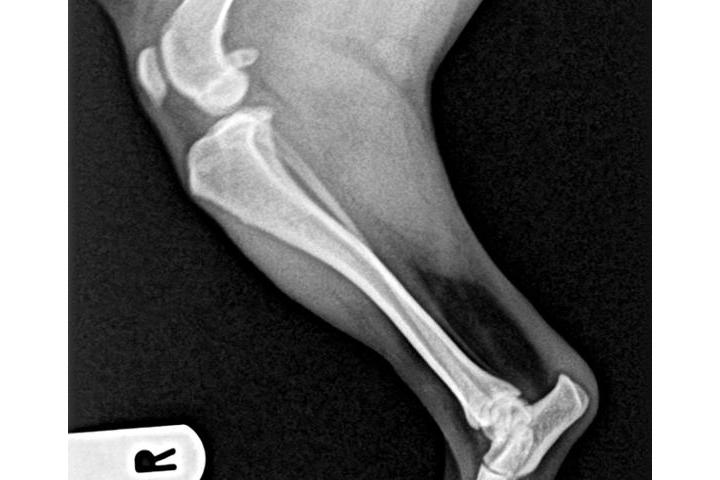

Actualisation sur la cause

Victoria Riera Serra

Teaming Manager

le 30/05/2017 à 17:50h

1a radio

Tengo buenas no tan buenas noticias...la adopción legal de Sólo se ha resuelto....ya es oficialmente nuestra....rstamos a la espera de la documentación para realizar el cambio de demarcación y censarla en Reus...por otro lado la visita al veterinario y las rx confirmaron el diagnóstico inicial...el grado de luxación de sus rótulas es muy grave y la cirugía es inevitable....estoy a la espera del informe del traumatólogo y del nuevo presupuesto para haceroslo llegar a todos; si bien es algo más económico que los dos anteriores sigue subiendo un pico. Habrá que operarprero una para y esperar para posteriormente operar la otra..de ese modo podrá llevar una vida relativamente normal hasta su total recuperación....la buena noticia es que no hay indicios de artrosis lo que significa que no hay dolor...una vez iniciado la primera intervención se valorará es estado de sus tendones para descartar un "tendón laxo"...a lo largo del día recibiré por mail el informe completo junto con una copia de las rx para poder mostraroslas....de nuevo gracias a todos por ayudarme a hacer posible el tratamiento de Snoopy